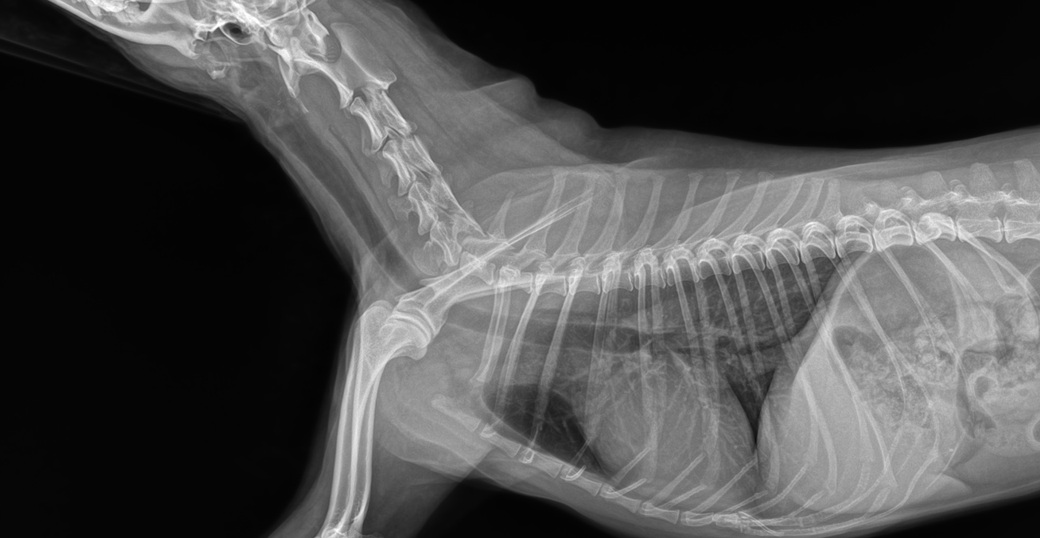

선생님 저희 강아지 허리디스크가 어느정도인가요?

한달에 한번 주기로 깨갱 거리면서 특히나 혼자 붕가붕가하고 나서 그러는데요

허리 디스크가 어느정도 상태인지 그리고 붕가붕가를 평생 못하게해야하는건지.. 알려주시면 감사하겠습니다....

허리디스크 진단은 엑스레이 촬영으로는 정확하게 알 수 없습니다.

신경쪽 질환의 진단은 MRI 촬영으로 하는 것이 가장 정확합니다. 하지만 비용이 굉장히 비싸고 약간의 허리 통증은 운동 제한과 내복약으로도 증상 관리가 잘 되는 경우가 많습니다.

경추와 흉요추부에 디스크 소인이 있는 양상이 관찰되고 있지만 디스크는 엑스레이 사진으로 평가하는 질환이 아닙니다.